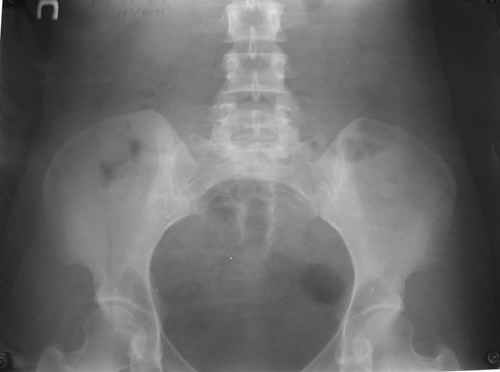

Уважаемые коллеги! Вопрос по уточнению диагноза. Методы дополнительной диагностики? Вашемнение по данному случаю?Спасибо!

Женщина, 30 лет.

Жалобы на сильные боли в суставах и мышцах (без четкой локализации), припухлость суставов, повышение температуры 38-39 гр.

Считает себя больной с 1994 г., когда появились боли в легких. В 1996 г. - боли в спине без четкой локализации. 2002 г. - роды, через 10 мес. сильные мышечные боли. 2004 г. - плеврит и увеит (сейчас - миопия, -1,-1,5, астигматизм). Периодические увеличения лимфатических узлов (чаще шейных), симптомы васкулита.

Диагноз: Ревматоидный артрит неизвестной этиологии (реактивный урогенитальный артрит или полиартрит?)